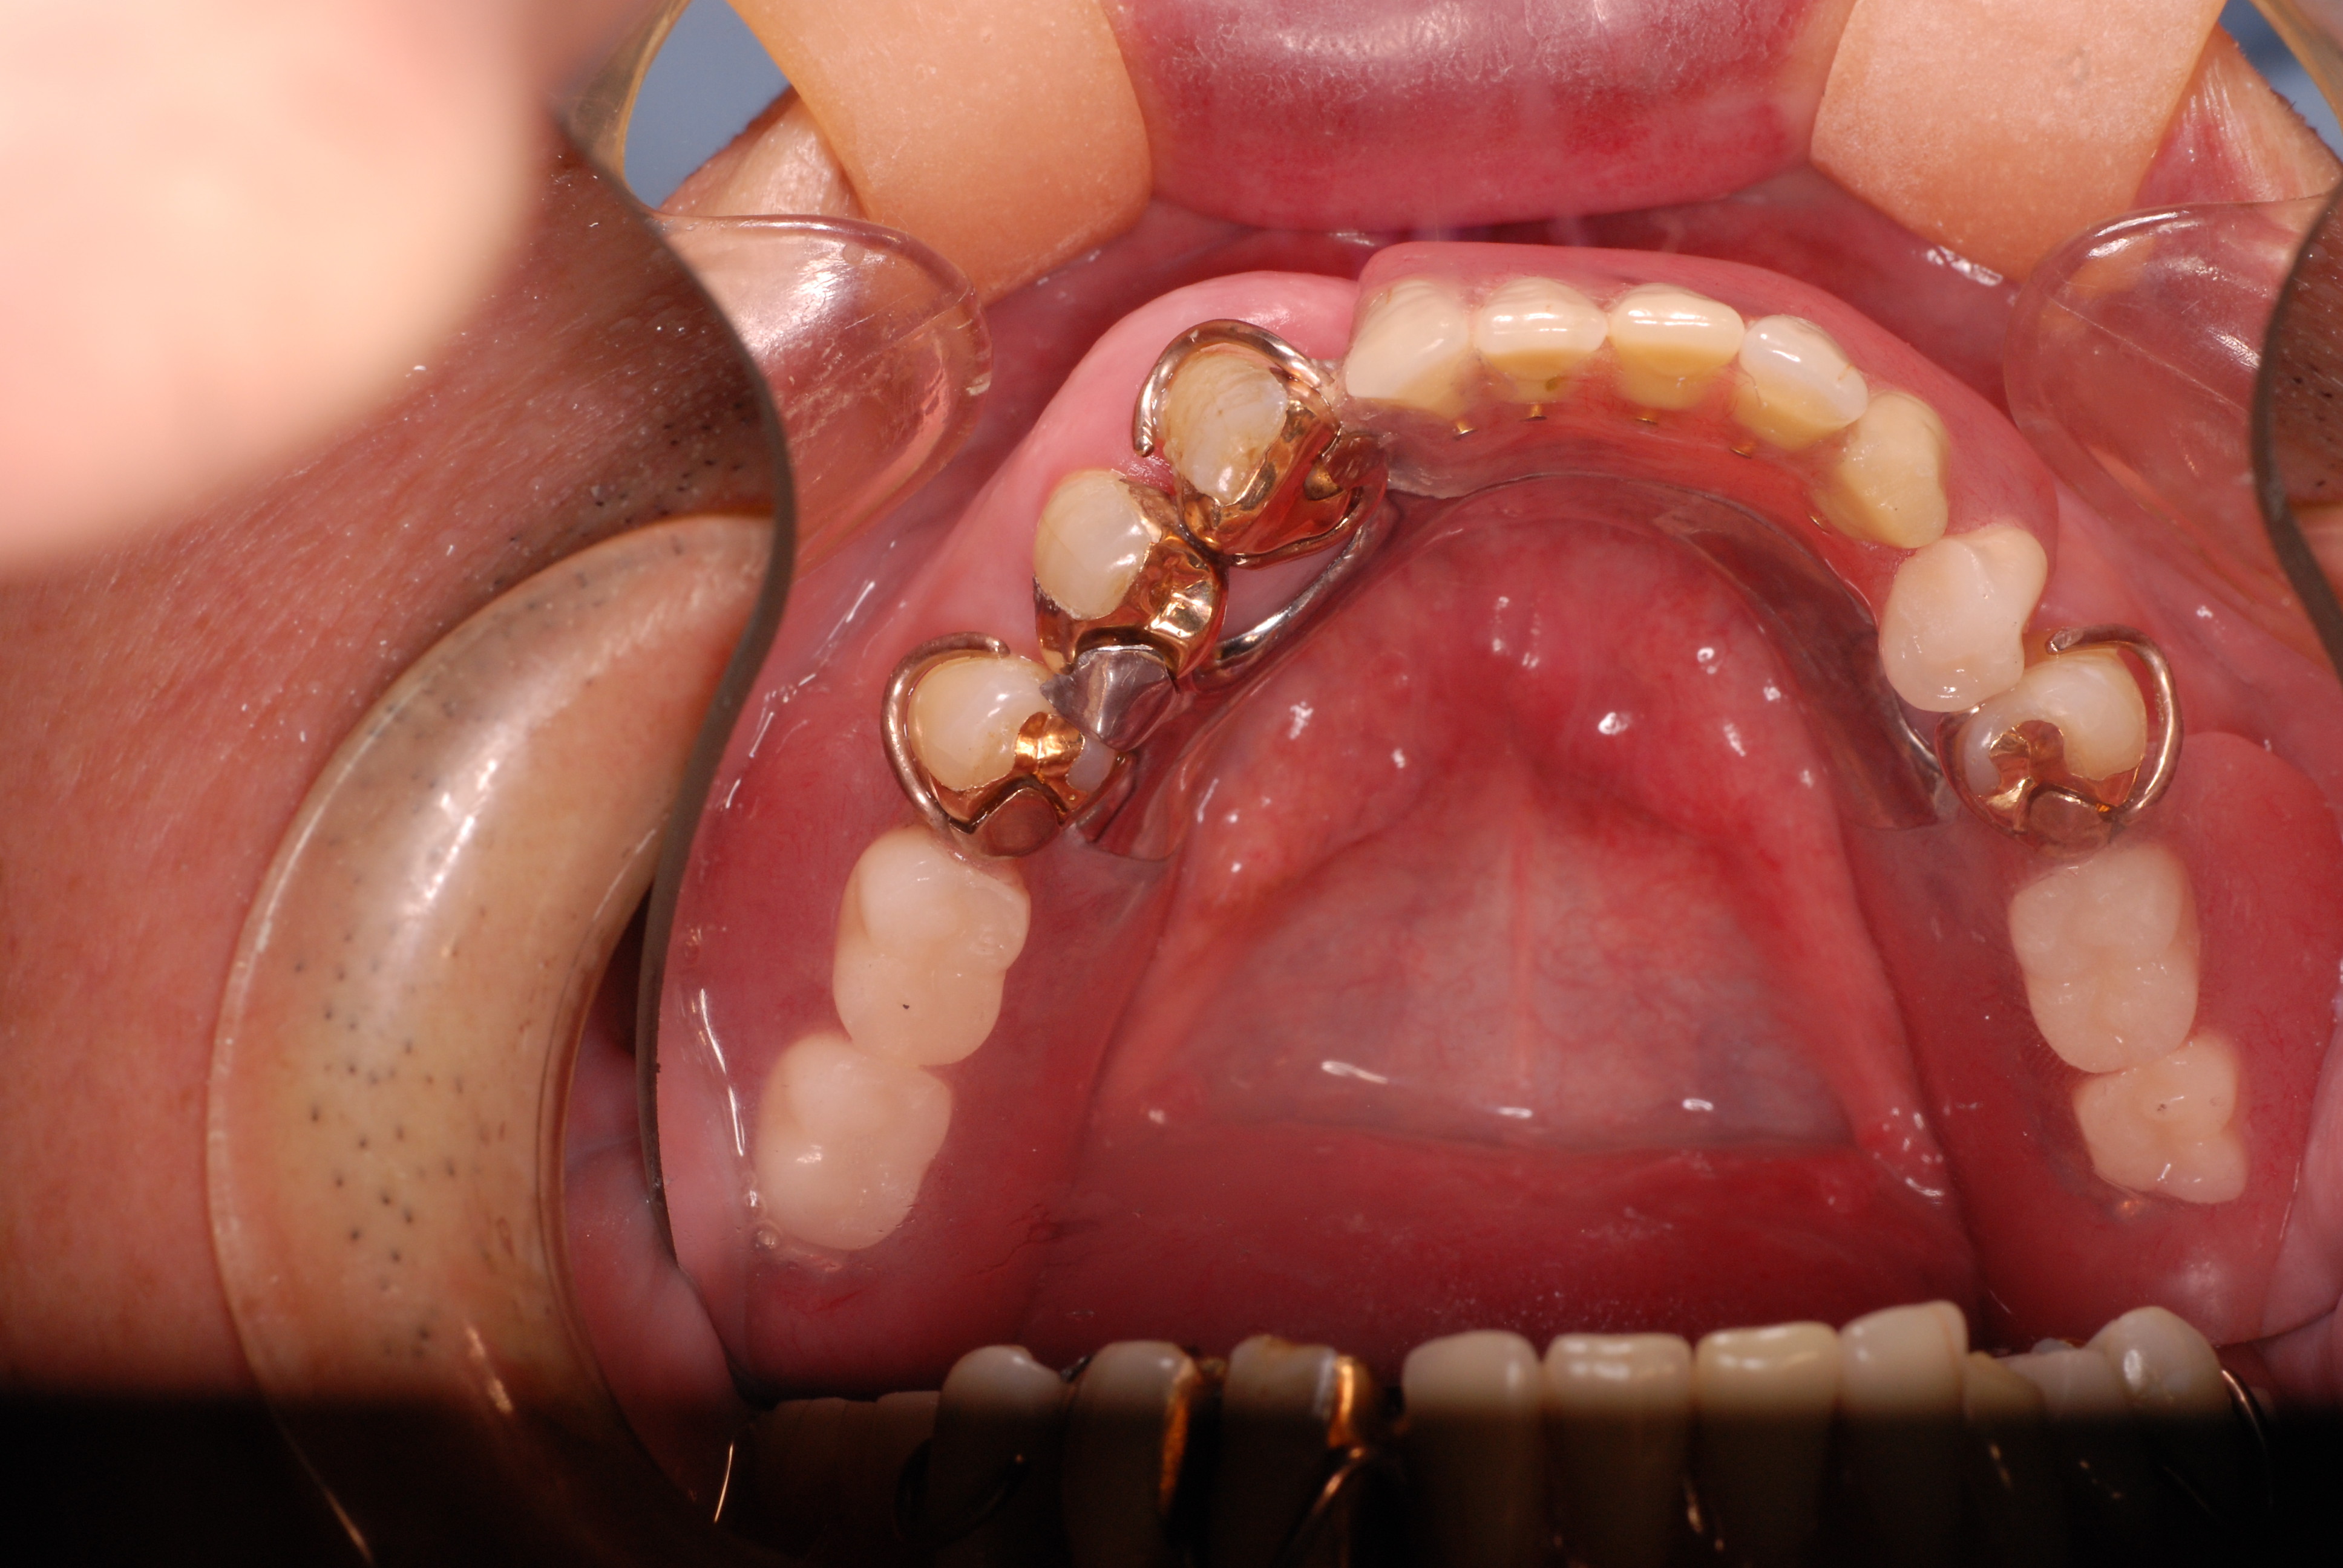

現実を見ればお口の中には“異物”である金歯、銀歯、セラミック、インプラントのオンパレードです。

これ等のものは、異物です。無い方が病気にならず健康でいられるのです。

必ずばい菌が侵入しないようにしてばい菌である虫歯を除去します。

銀歯の下はばい菌だらけです。こういうのはよくあります。取り残しですね。![treatment_05[1]](https://livedoor.blogimg.jp/netdental/imgs/3/a/3ad019d0-s.jpg)